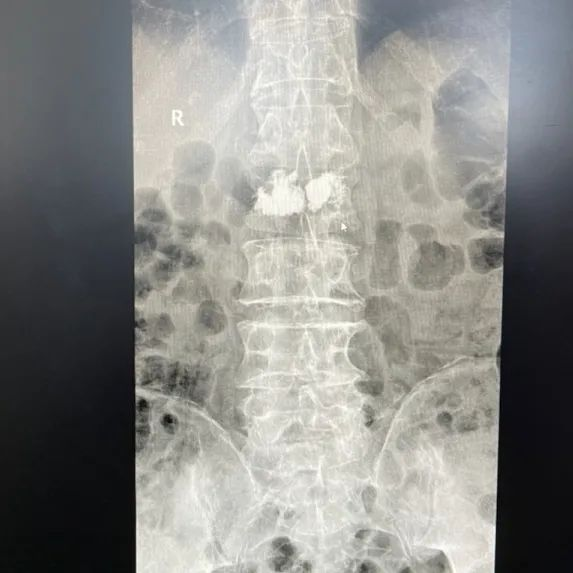

不久前,89岁高龄的翟老太不慎跌伤,导致腰椎骨折,因为剧烈疼痛,老人不能坐也不能站,只能侧卧在床,连翻身、吃饭都很困难。看到蜷缩在床上不断呻吟的老人,家人焦急万分,听说姜堰中医院骨伤科陈成团队擅长治疗腰部损伤,急忙将老人送到我院骨科就诊,经医生诊断翟老太系腰椎骨折。

翟老太被收治到我院八病区后,脊柱骨科夏国栋副主任医师为老奶奶制定了详细的诊疗方案,决定采用经皮椎体成形术为老人手术。一听说要手术,躺在病床上的翟老太就急了,连连摆手,嘟囔着说“不,不...”夏国栋医师笑着安慰老人及家属,并详细解释了经皮椎体成形术的手术方法,消除了翟老太和家人对手术治疗的疑虑。夏国栋诊疗组的专家在手术室给翟老太腰上打了“一针”,手术时间仅20多分钟,回到病房的翟老太腰部疼痛消失,当天就基本恢复到受伤前的状态。立竿见影的手术效果令翟老太的家人们啧啧称奇!出院后的翟老太嘱咐家人给医生送来锦旗。

翟老接受的经皮椎体成形术(percutaneous vertebro plasty,PVP),属于微创手术,是通过精确定位向病变椎体内注入骨水泥(聚丙烯酸甲酯,polymethylacrylate,PMMA)达到治疗作用的技术。此种手术通常采用局部麻醉,麻醉风险低,手术伤口约2毫米,出血约5-10ml,手术时间20-30分钟左右。术后就能感觉腰痛减轻,第二天就能起床活动,逐渐恢复起居、行走等日常活动。

据了解,对于老年腰椎骨折,传统治疗多采用保守治疗,要求绝对卧床3月加药物治疗。但是老年人往往伴有高血压,糖尿病,心脏病等基础病,长期卧床容易并发肺部感染、血栓、褥疮、尿路感染、感染性休克等疾病,继而危及生命。近年来,微创化手术逐渐成为此类疾病的主流方案,经皮椎体成形术技术可以稳定脊柱、快速止痛、见效快、效果好,可大大减少患者的卧床时间,明显提高患者的生活质量,帮助患者早日恢复正常生活。夏国栋副主任医师所在的姜堰中医院脊柱骨科具有脊柱微创手术成熟的技术,大量脊柱骨折病人在微创手术后像翟老太一样撑起了脊梁,恢复了健康。